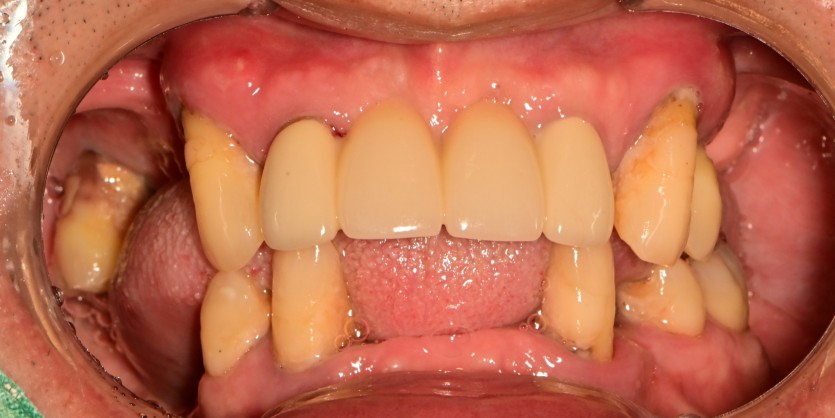

전체 임플란트 증례입니다.

18개의 임플란트로 완성하였습니다.